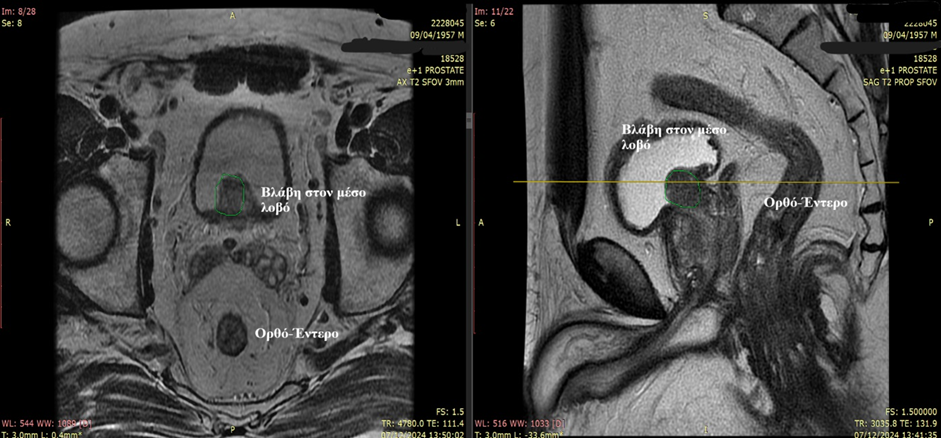

Πώς βοηθάει η πολυπαραμετρική μαγνητική στη διάγνωση του καρκίνου του προστάτη και στη βιοψία; (Βλ. Εικόνα 1)

Εικόνα 1: Σχεδιασμός του προστάτη (κόκκινο σχεδιάγραμμα) και σχεδιασμός της βλάβης (μπλε σχεδιάγραμμα).Με τον τρόπο αυτό σχεδιάζεται η βλάβη και ο ουρολόγος εν συνεχεία με την Fusion βιοψία προστάτη λαμβάνει στοχευμένες βιοψίες (Εικόνα από την συλλογή της Medcom).

Κατά την πραγματοποίηση της βιοψίας δεν αρκούν οι εικόνες της μαγνητικής αλλά ο ουρολόγος οφείλει να γνωρίζει να ερμηνεύει τις εικόνες αυτές και να σχεδιάζει από μόνος του τις ύποπτες περιοχές στο ειδικό λογισμικό της Fusion βιοψίας (Βιοψία σύντηξης εικόνων σύστημα BiopSee-Medcom) το οποίο εν συνεχεία κατευθύνει τον ουρολόγο να λάβει βιοψίες από τις σχεδιασμένες ύποπτες περιοχές. Το λογισμικό δηλαδή κατευθύνει τον ουρολόγο να λάβει βιοψίες από τις περιοχές που αυτός σχεδίασε με βάση τις υποδείξεις της μαγνητικής και βέβαια με βάση την προσωπική του γνώση ερμηνείας της μαγνητικής. Αν ο ουρολόγος σχεδιάσει λάθος τις ύποπτες περιοχές τότε το λογισμικό της Fusion βιοψίας προστάτη θα τον κατευθύνει λάθος. Για το λόγο αυτό είναι σημαντικό η βιοψία να πραγματοποιείται από ουρολόγους εκπαιδευμένους που είναι άριστοι γνώστες ερμηνείας των εικόνων της μαγνητικής με εμπειρία στην συγκεκριμένη τεχνική.

-Οι ουρολόγοι της ομάδας Advanced Urology ( Δρ.Ιωάννης Λεωτσάκος & Δρ.Ι.Καταφυγιώτης) τοποθετούν το CD της μαγνητικής στο ειδικό μηχάνημα με το κατάλληλο λογισμικό(BiopSee-Medcom) και κάνουν τον σχεδιασμό του προστάτη και των βλαβών.(Βλ.Εικόνες 5 & 6)

Εικόνα 6: Πολυπαραμετρική μαγνητική τομογραφία προστάτη με σχεδιασμό του προστάτη (Κόκκινο πλαίσιο) και ξεχωριστό σχεδιασμό της βλάβης (Μπλε Πλαίσιο).Ο προστάτης και η βλάβη αρχικά σχεδιάζονται και είναι ιδιαίτερα σημαντικό ο ουρολόγος να έχει την κατάλληλη εκπαίδευση στην ερμηνεία των εικόνων της μαγνητικής.